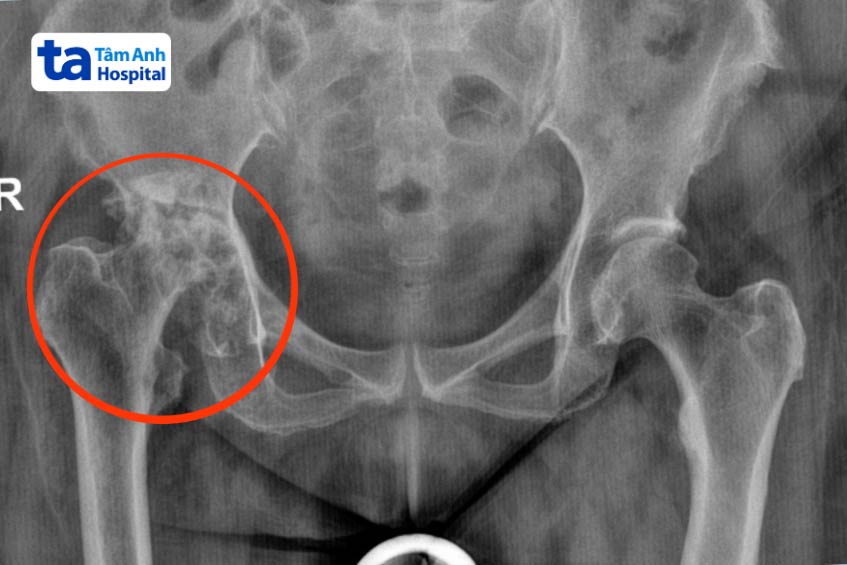

Chị Trinh bị hư hoại hoàn toàn chỏm xương đùi, chỉ còn lại cổ xương đùi. Trong quá trình sinh hoạt hàng ngày, cổ xương đùi không ngừng va chạm và khoét rộng ổ cối, gây mất xương ổ cối nghiêm trọng. Hơn hai năm gần đây, người bệnh không thể đi lại, phải ngồi xe lăn.

Theo bác sĩ Khoa, khớp háng được cấu tạo từ hai thành phần chính là chỏm xương ở đùi có hình cầu và ổ cối ở xương chậu, lõm vào như cái chén, bao bọc chỏm xương đùi. Ở trường hợp bị nặng mất hoàn toàn ổ cối xương đùi như chị Trinh, nếu thay khớp theo các phương pháp thông thường, có thể phải cắt cơ và cần lấy xương từ vị trí khác để bù vào phần khoét hổng ở ổ cối. Điều này làm người bệnh đối mặt với nguy cơ mất máu và kéo dài thời gian phẫu thuật, gây tổn thương gan.

Phần khuyết hổng ở ổ cối quá lớn nhưng không thể lấy xương ở vị trí khác bù vào vì sẽ gây mất máu. Do đó, thông qua đo đạc và tính toán trên phần mềm TraumaCad, bác sĩ Khoa đã thay khớp háng nhân tạo kỹ thuật Jumbo Cup với đường mổ ABMS. Jumbo Cup là kỹ thuật thay loại khớp đặc biệt, có ổ cối to hơn so với ổ cối tự nhiên của người bệnh, bao phủ toàn bộ phần ổ cối đã mất xương. Vì vậy, không cần phải lấy xương từ các vị trí khác và góp phần cầm máu ở khớp háng. Ngoài ra, ổ cối to còn giúp tản lực tốt, người bệnh có thể sớm tập phục hồi chức năng và tăng tuổi thọ khớp nhân tạo.